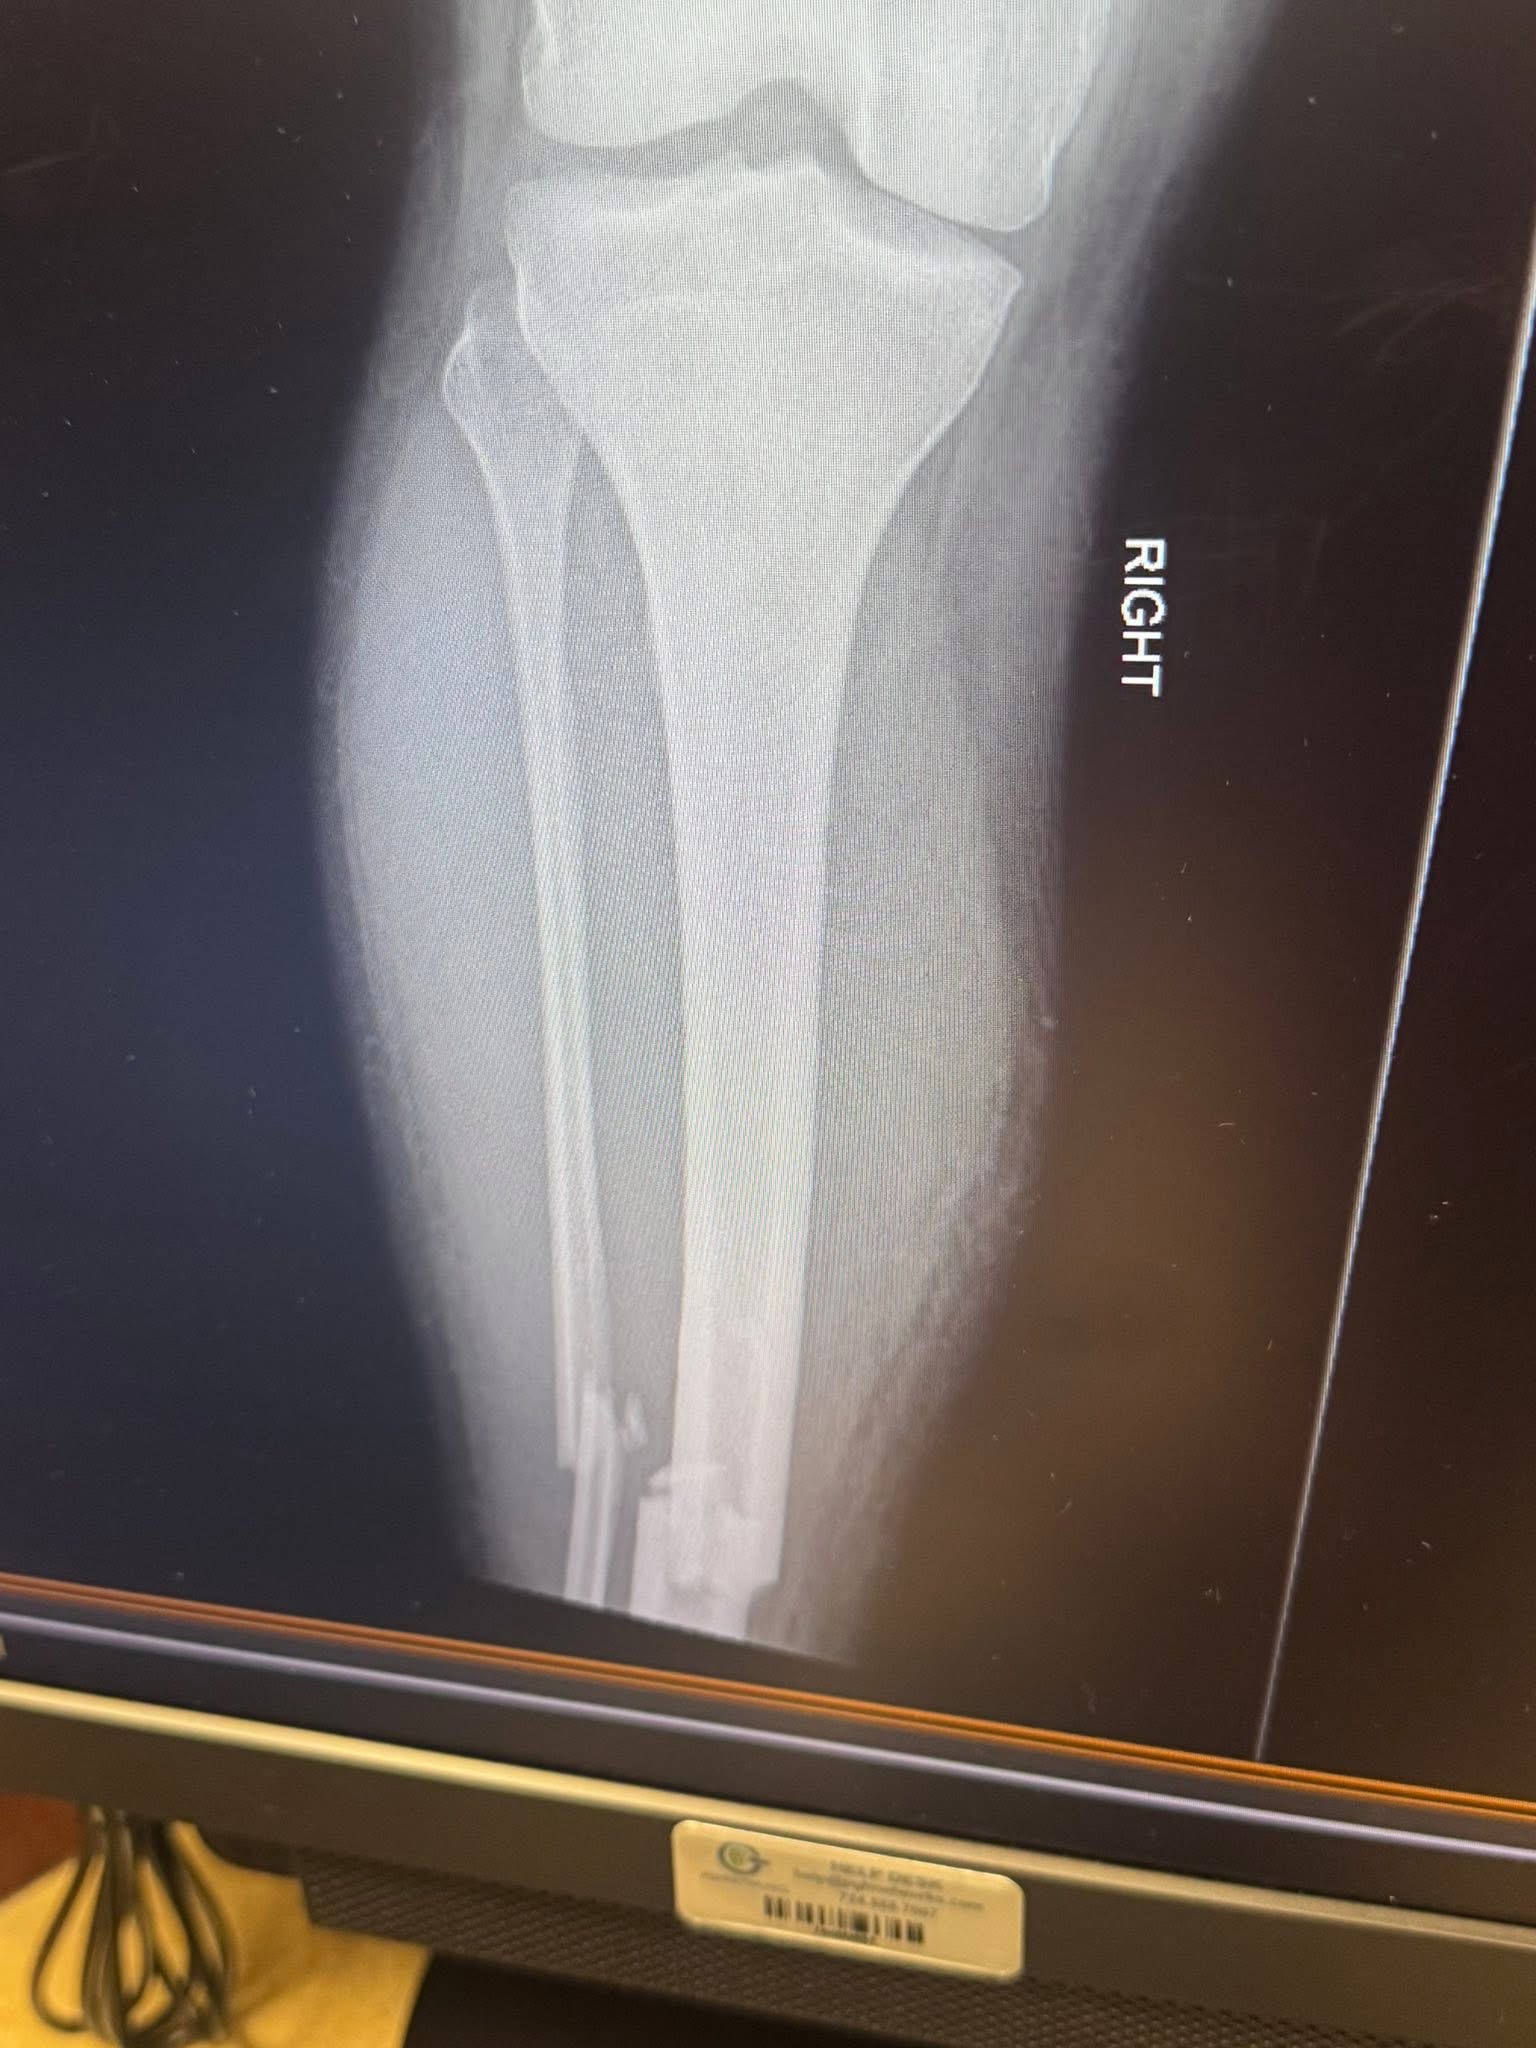

Just a little update. Logan is home he’s doing good they ended up putting 2 nails and 5 screws in his leg. His job is going to give him a desk job until he’s better and the doctor said after about a month of rehab he should be good to go back to work even though at first it will just be working in the office. Then overall probably a little over 3 months till he will pretty much be fully good to go. I’m glad that God worked things out and that Logan is doing good. ❤️